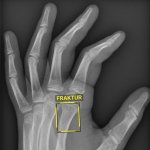

Frakturen in Sekunden erfassen und markieren: Ein neues KI-Assistenzsystem hilft seit Kurzem in der Radiologie der Universitätsmedizin Göttingen bei der Auswertung von Röntgenbildern.